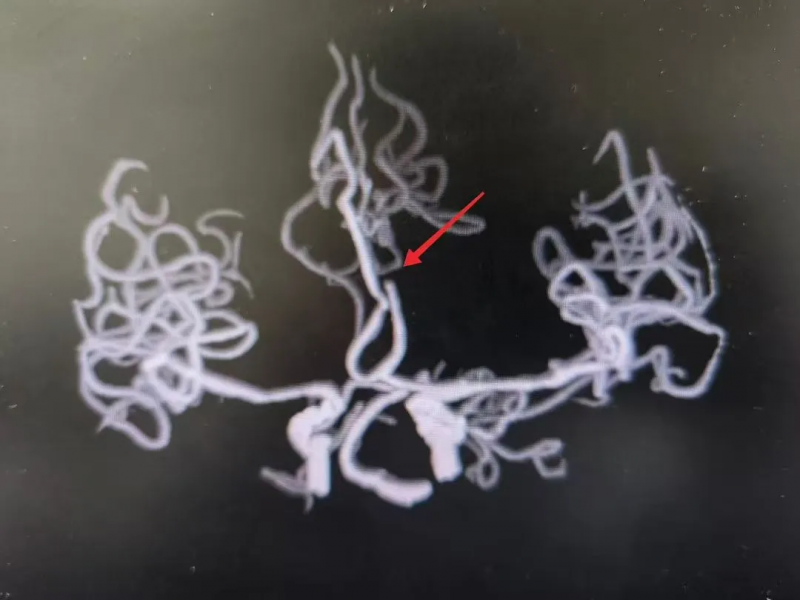

放射科

CT/MR室